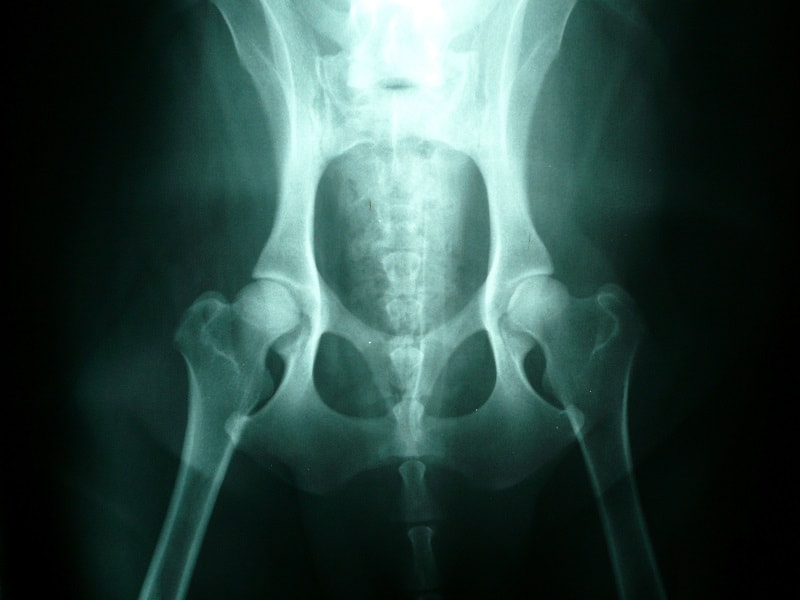

Displasia de cadera

Típica de perros grandes como mastín o pastor alemán y es hereditaria. La displasia de cadera puede presentarse en jóvenes, por lo que es aconsejable realizar radiografías para un diagnóstico precoz, en los perros viejos también es frecuente.

El acetábulo hueco es el hueco en la pelvis que aloja la cabeza del fémur. En la displasia, este hueco y la cabeza del fémur se van deformando hasta que la cabeza entra y sale del acetábulo. Esto produce dolor y cojera, los perros no desean saltar y toleran menos el ejercicio o les cuesta levantarse y subir escaleras. Su marcha suelen ser balanceante, cambian el peso evitando apoyar la extremidad que les duele.